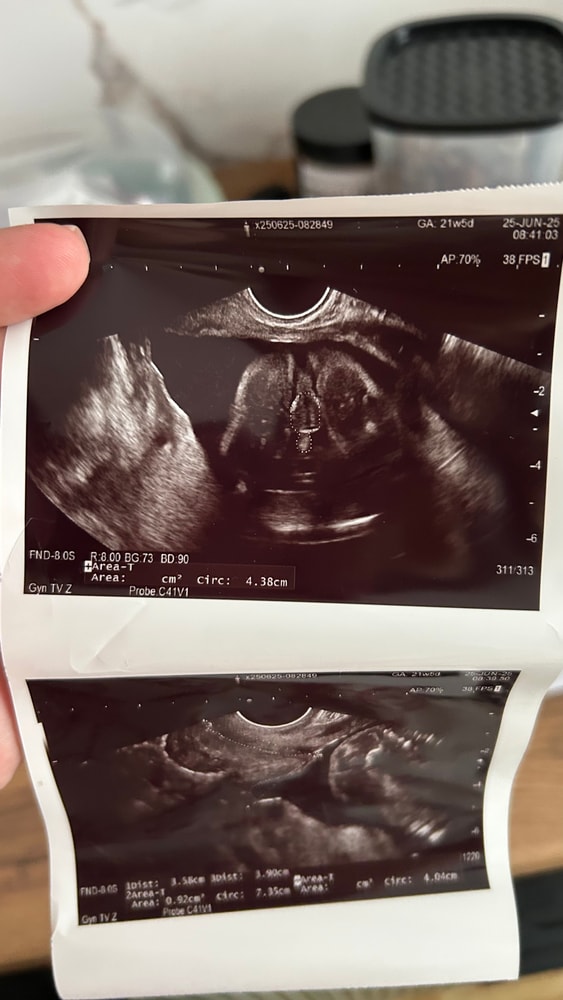

2 скрининг в 20.3

В итоге все показатели в норме, показали абсолютно все, ручки, ножки, носик, пяточки🥰 про каждый из показателей подробно рассказали, на что больше внимания обратить) Уже столько узи у меня было, я до сих пор не могу поверить, что внутри меня такой карапузик.

Специально для папы сделали фото, а то ему сложновато было поверить, что там не девочка😁